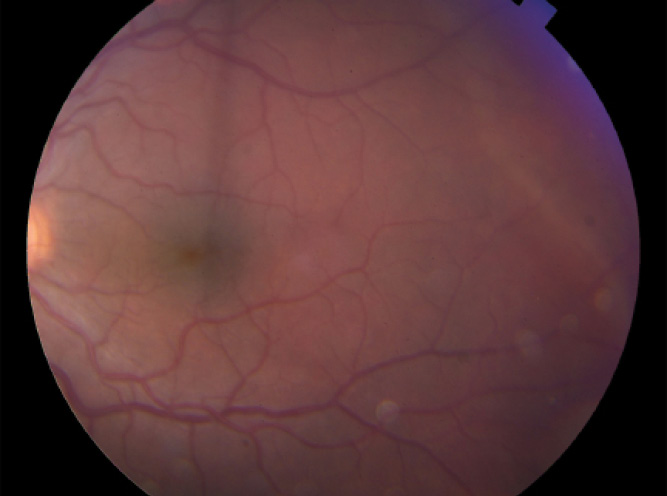

Figure 5. Fundus image of the left eye of a child shows a superotemporal retinal detachment due to a dialysis that occurred 11 months after the patient underwent vitrectomy and received intravitreal antibiotics for endophthalmitis 2 days after repair of corneal laceration.

Patients With Chronic Retinal Detachment

For patients with chronic retinal detachments associated with ocular trauma and peripheral retinal breaks (Figure 5), we often place a scleral buckle initially, perform limited cryotherapy to surround the retinal breaks, and then drain subretinal fluid externally to effect a good buckle contour. It can be difficult for a child to fulfill postoperative positioning requirements after vitrectomy, so performing a buckle without vitrectomy minimizes the stringent positioning required.